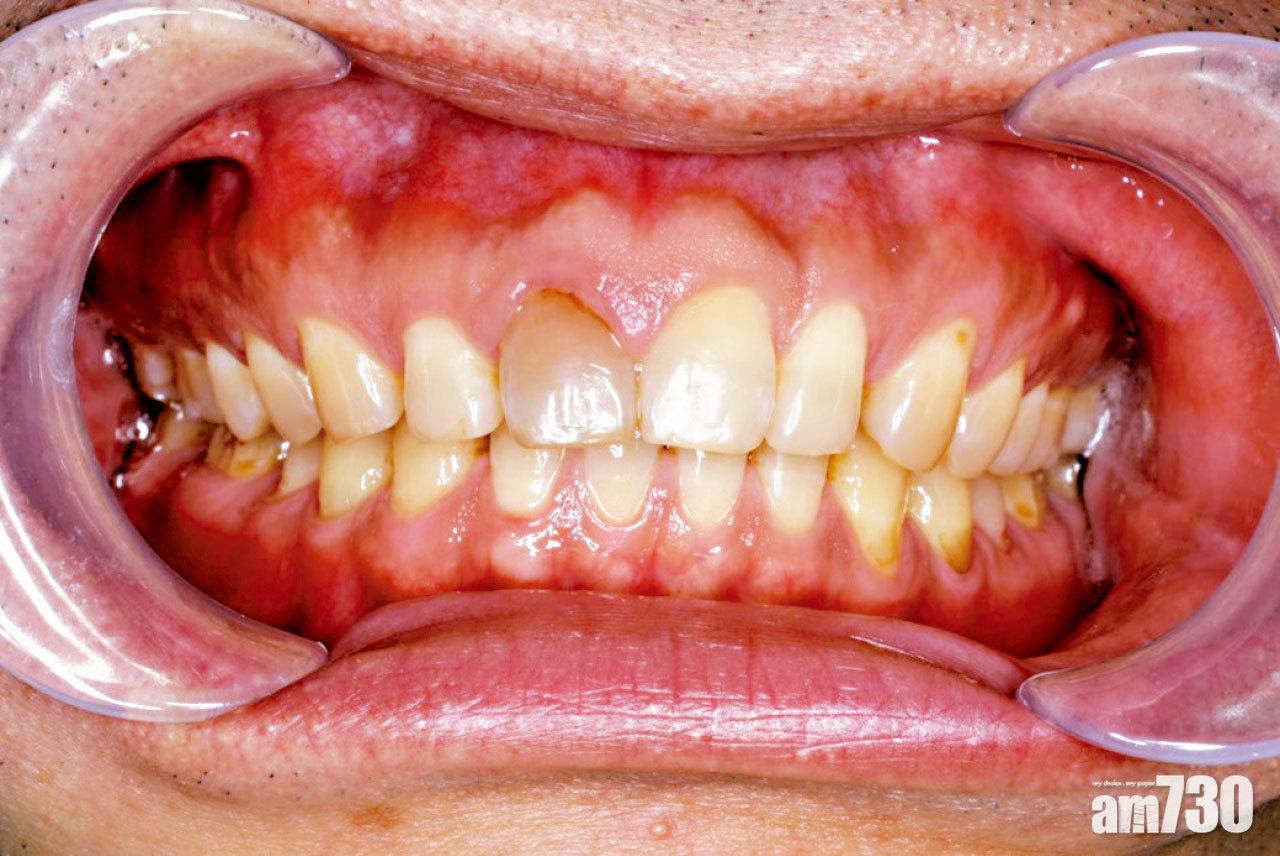

使用全自助隱形牙箍,有牙齒壞死的風險。

楊日昌續指,使用隱形牙箍時,牙醫會因應需要加入附件,增加「扶手」位置助移動牙齒,又或者將牙推後、磨細、脫牙等,「如沒有牙醫的話,以上東西都做不到,令箍牙的效果打了折扣;不過最重要的是,有牙醫緊密監察的話,萬一有問題發生可以及早發現及早處理,如果沒有牙醫,就容易令問題發展至愈來愈差。會遇到的問題包括牙箍不適合或不貼合、後牙開咬,較嚴重的可能會有牙槽骨吸收、牙根露出,甚至牙齒壞死。要解決這些嚴重問題,往往需要數個牙醫專科處理,而且未必可回復最初樣子,實在得不償失。」